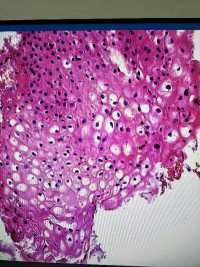

CIN1?

图1

图2

图3

图4

LSIL。

其实lsil的诊断一致性很低,上海的标准诊断lsil比较严格,似是而非者为非,本例属于似是而非,按我们的日常则争议比较多,我觉得综合看吧,阴道镜表现,hpv和tct检测结果来综合判断。

谢谢各位老师,TCT报ASCUS,患者自述HPV59阳